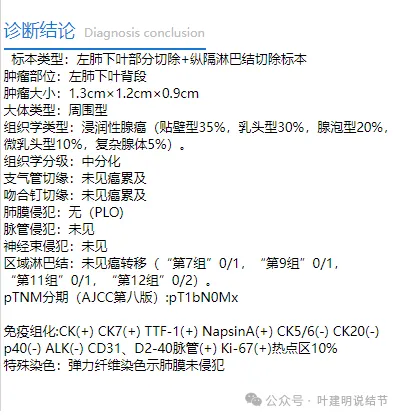

术后常规病理示:浸润性腺癌,贴壁型35%,腺泡型20%,微乳头10%,复杂腺体5%。中分化,胸膜,支气管切缘以及脉管均阴性。淋巴结采样第7组、第9组、第11组以及第12组未见转移。

此例有15%高危亚型,略显不放心。但目前TNM分期,仍属1A2期,T1bN0M0。对于是否需要术后再升级肺叶切除或是否需要术后辅助治疗。我的想法是:1、病灶按目前分期仍是1A2,指南是不建议术后辅助治疗的;2、从此灶长达5年的随访,而且进展并不显著来讲,恶性程度不可能是很高,若是恶性程度高的类型,不要说5年,半年一年就广泛转移了。所以危险性高低一看影像表现,二看病理类型,三看随访进展情况。金标准是病理,但归根到底还是随访进展快不快。五年不怎么长的实性为主的结节,管它病理类型是什么,总不至于高度恶性。所以个人不倾向再切肺叶,也不倾向术后辅助化疗或靶向治疗。现在的肺癌真的与以前不一样了!根本没有干预处理五年过去了,仍是早期,更别说磨玻璃肺癌了。所以呀,在评估肺癌治疗效果的时候,仍沿用五年生存率看来是时候该适当改改了。